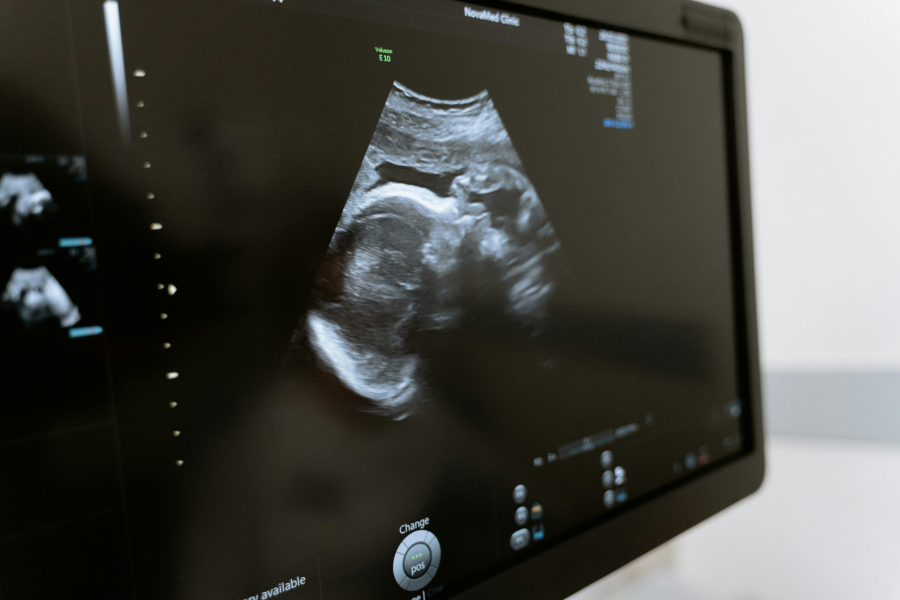

Καθώς λοιπόν είχε προγραμματιστεί η υστερεκτομή για την αφαίρεση της μήτρας του, ανακαλύπτουν την εγκυμοσύνη οι γιατροί σε νοσοκομείο της Ρώμης.

Θεωρείται ότι είναι η πρώτη περίπτωση του είδους της στην Ιταλία, η αιφνιδιαστική ανακάλυψη έχει εγείρει ανησυχίες για την ευημερία του μωρού και για το κατά πόσον το έμβρυο έχει επηρεαστεί από τις διαδικασίες στις οποίες έχει υποβληθεί μέχρι σήμερα ο Μάρκο.